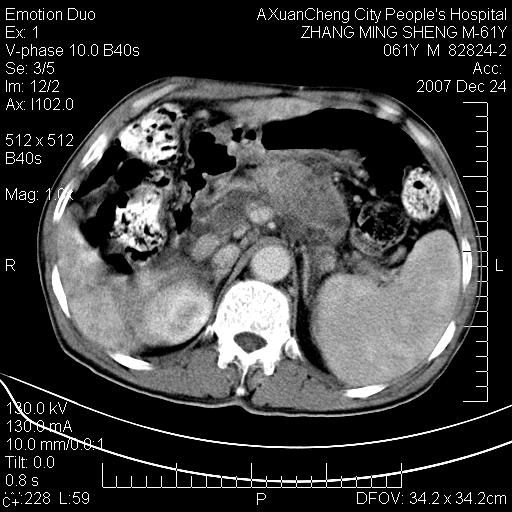

标题: CT11031:M61Y,胰腺占位

大家侃侃门静脉和胆管系统怎么回事,肝内转移?

1,肝硬化,脾大.

2,肝内多发结节状低密度占位,伴门脉及肠系膜上v栓子形成.考虑a;门脉及肠系膜上v血栓后肝改变.b;弥漫型肝癌伴门脉及肠系膜癌栓.

肝硬化,门脉高压,脾肿大;弥漫性肝癌,肝内、门脉、腹膜后淋巴结转移,肝内外胆管扩张,胰头区占位,建议mr检查

胰腺癌伴肝内转移;门脉、肠系膜上v癌栓形成。

考虑为:胰腺癌伴肝脏转移、腹膜后淋巴结转移,门静脉及肠系膜上静脉瘤栓形成。

胰体尾癌伴肝内转移,门静脉及肠系膜上静脉瘤栓形成.

肝硬化,脾大. 胰腺癌伴肝内转移;门脉、肠系膜上v癌栓形成。